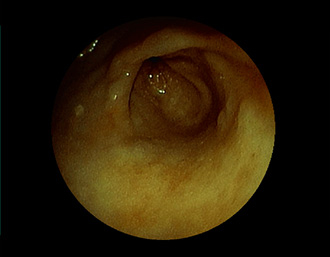

胃潰瘍(Stage S1)・・治療後5ヶ月

潰瘍の中心に白苔はなく、わずかに陥凹する潰瘍面に発赤が残る再生上皮が覆い尽くす(赤色瘢痕)。集中皺襞がなだらかに中心に延びている。→ ヘリコバクター・ピロリ感染を認めたため、除菌治療で駆除しました。